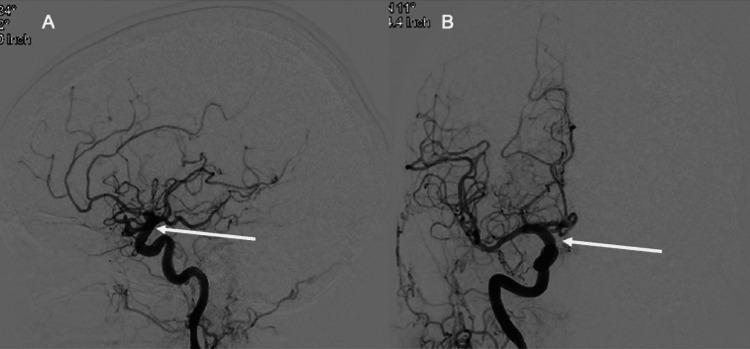

Ruptured cerebral aneurysms can cause significant morbidity and mortality. Endoluminal devices to treat aneurysms such as the Pipeline™ Flex Embolization Device with Shield Technology (PFES) (Medtronic, Dublin, Ireland) integrate phosphorylcholine on the surface of the device in order to reduce platelet adherence that causes periprocedural thromboembolic events and subsequent long-term intrastent stenosis. In addition to the Shield Technology, patients are commonly placed on dual antiplatelet therapy (DAPT) for six months to reduce thromboembolic events and subsequent long-term intrastent stenosis. There is a strong positive correlation between the length of DAPT use and bleeding. Here, we present a case of a 66-year-old female with a right supraclinoid internal carotid artery (ICA) aneurysm treated with a PFES who was placed on dual antiplatelet therapy for the first 31 days postoperative and subsequently maintained on aspirin (ASA) 81 mg monotherapy. At two months, a follow-up diagnostic cerebral angiogram showed complete occlusion of the aneurysm with a patent stent. Our case sets the stage for further research into the optimal length of dual antiplatelet therapy required in PFES to prevent short and long-term thromboembolic events. This report indicates that it may be safe for patients with PFES to intermittently halt the use of DAPT to manage bleeding complications or perform surgery.

破裂的脑动脉瘤可导致严重的发病率和死亡率。用于治疗动脉瘤的腔内装置,如带有护盾技术的Pipeline™ Flex栓塞装置(PFES)(美敦力公司,爱尔兰都柏林),在装置表面整合了磷酸胆碱,以减少导致围手术期血栓栓塞事件和随后长期支架内狭窄的血小板粘附。除了护盾技术外,患者通常还需接受六个月的双联抗血小板治疗(DAPT),以减少血栓栓塞事件和随后的长期支架内狭窄。DAPT使用时间长短与出血之间存在很强的正相关性。在此,我们报告一例66岁女性,其右侧床突上段颈内动脉(ICA)动脉瘤采用PFES治疗,术后前31天接受双联抗血小板治疗,随后维持阿司匹林(ASA)81mg单药治疗。两个月时,随访诊断性脑血管造影显示动脉瘤完全闭塞,支架通畅。我们的病例为进一步研究PFES预防短期和长期血栓栓塞事件所需的最佳双联抗血小板治疗时长奠定了基础。本报告表明,对于使用PFES的患者,间歇性停用DAPT以处理出血并发症或进行手术可能是安全的。